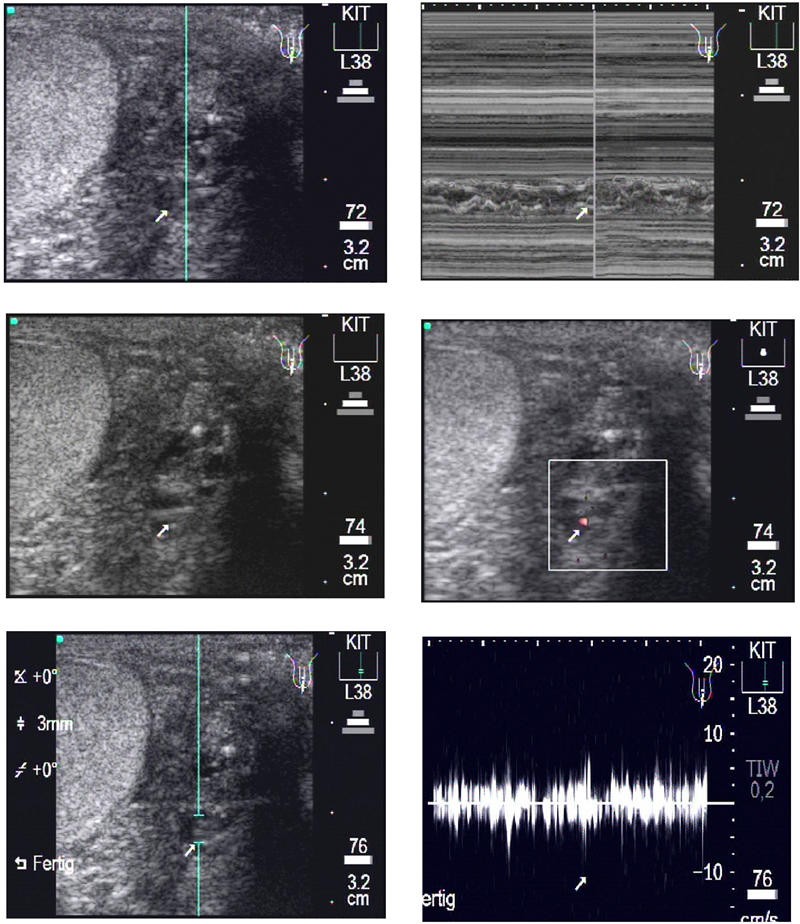

Figure 3

From: Animated documentation of the filaria dance sign (FDS) in bancroftian filariasis

Longitudinal scan of a patient's left testis. Upper left: A medium sized para-testicular worm nest (arrow) is presented in this b-mode image. Upper right: The following m-mode section is positioned at the location of the largest diameter of the worm nest. The corresponding video image can be seen as Additional File 7: Movie3A.mpg. Middle left: The same worm nest as above. Middle right: The Colour Doppler-mode presents very few red signals as sign of less lymphatic fluid moved by the adult worms in this dilated lymphatic vessel. The corresponding video image can be seen as Additional File 8: Movie3B.mpg. Lower left: The same worm nest as above. The caliper for the PWD is positioned where the worm nest is located. Lower right: The Pulse Wave Doppler-mode confirms the medium sized worm nest by the irregular undulating band caused by the typical movements of the adult worms. The corresponding video image can be seen as Additional File 9: Movie3C.mpg.